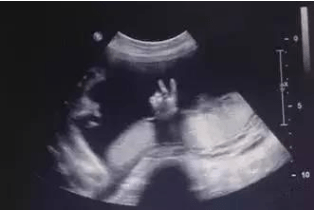

胎儿系统超声作为孕中期最重要的一项排畸检查 , 也被宝妈们所熟知 , 被称作“大排畸”检查 。 这是第一次在宫内对宝宝进行全身的、各个系统的、从头到脚的大体检 。 胎儿系统超声检查其实也包括了对宝宝心脏结构畸形的排查 , 但是它仅针对常见的心脏结构平面进行排查 。 胎儿系统超声检查包括了胎儿四腔心切面、左室流出道切面、右室流出道切面、三血管切面 。 主动脉弓切面等一些常见的、比较容易观测到的切面进行排查 。

那么对于有特殊情况、特殊病史的人群 , 是需要在原有的系统超声的基础上加做胎儿心脏超声的 。 比如:曾经怀过或生过先心性心脏病患儿、孕妇及家属本人有先心病家族史、或者孕妇由于自身免疫性疾病等情况服用药物等特殊情况 。

胎儿心脏超声对于胎儿的体位、母体腹壁厚度、羊水量等很多因素是有一些重要的、严格的要求的 。 同时 , 也对我们的超声医生有较高的技术要求 。